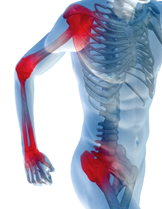

Manuál terápia. Ízületi gyulladás és kezelése. Mágnes terápia

Izom fájdalom kezelése→manuál terápia Mozgás beszűkülés

javítása. A terápia teljesen biztonságos, fájdalmatlan és gyorsan hat. Az ízületi

gyulladás okozta fájdalmat a Motion Energy gél jelentősen csökkenti. Étrenddel

az ízületi gyulladás ellen. Omega-3 zsírsavak gyulladáscsökkentő

hatásuknak köszönhetően csillapítják az ízületi fájdalmakat. A lágylézer

terápiában alacsony energiájú, infravörös lézersugárral történik a kezelés. A

lökéshullám-terápia fókuszált, nagy intenzitású hanghullámmal történik. Az ultrahang

kezelés az alábbi betegségekre különösen alkalmas: -Ízületi betegségek, -

Lumbágó, - Csípő betegségek. Orvostechnikai eszköz: CE0483, a BEMER

készülék (foto) bérelhető. Mágnes terápia hatása –Csontrendszer, -Izomrendszer,

-Légzőszervi rendszer, -Ideg rendszer, -Keringési rendszer